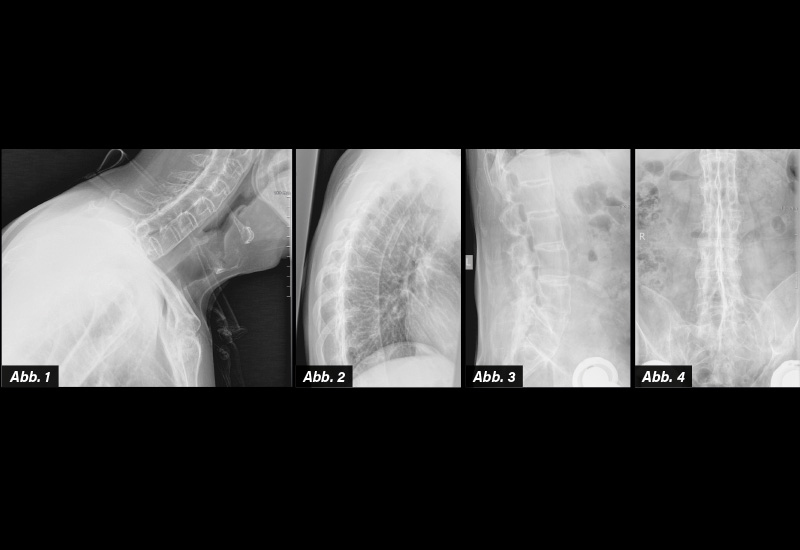

DIAGNOSE: Vollbild einer multisegmentalen AS mit Längsbandverkalkung, Syndesmophyten und Ankylose der ISG

BEMERKUNGEN ZUR BILDGEBENDEN DIAGNOSTIK: Röntgen: In allen Stadien der Spondyloarthritis (SpA), insbesondere natürlich in fortgeschrittenen Fällen, fällt eine diffuse Osteopenie auf. Charakteristisches Kennzeichen der SpA ist eine bilaterale symmetrische, gegebenenfalls zu Beginn der Erkrankung asymmetrische Gelenksspalterweiterung und im weiteren Verlauf dann -verschmälerung. Es lassen sich subchondrale Erosionen und Sklerosen nachweisen. In fortgeschrittenen Fällen kommt es zu einer Ankylose (ISG-Arthritis Grad IV) (Abb. 4). In frühen Phasen lassen sich glänzende Ecken (shiny corners) im Bereich der vorderen Wirbelkörperkanten entdecken (Romanus-Läsionen). Im Verlauf kommt es zur Ausbildung von Kastenwirbeln und zu einem späteren Zeitpunkt zu dünnen vertikalen Syndesmophyten, ausgehend vom Annulus fibrosus(Abb. 1-3). Langstreckige Fusionen im Bereich der Wirbelkörper und Facettengelenke kommen in späteren Stadien der Erkrankung zur Ausbildung und werden dann als Bambusstabwirbelsäule bezeichnet. Durch Fusion und krankheitsbedingte Osteoporose ist das Risiko von Wirbelkörperquerfrakturen erhöht, die im Röntgen nur schwer nachweisbar sind. Am häufigsten treten diese auf im zervikothorakalen sowie thorakolumbalen Übergangsbereich.